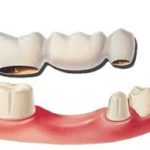

As you journey through life, your oral health evolves, marking significant milestones along the way. One crucial dental event typically occurs between the ages of 17 and 21 – the emergence of wisdom teeth, also known as third molars. These teeth earned their moniker due to their appearance during a more mature stage of life.

When they emerge correctly, healthy wisdom teeth contribute to efficient chewing. While slight discomfort is normal during their eruption, it’s essential to promptly consult your dentist if you experience persistent pain. Don’t wait! Take proactive care of your oral health and schedule your appointment today to ensure a brighter, pain-free smile for the future.